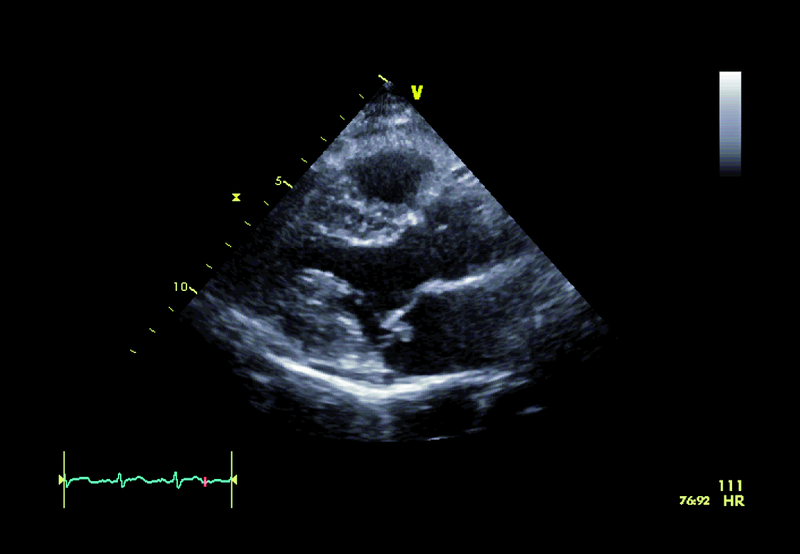

Badanie przezklatkowe, które jest badaniem pierwszego wyboru w przypadku podejrzenia zapalenia wsierdzia, potwierdza obecność dodatkowego echa na strukturach zastawki mitralnej (ryc. 1, 2). Wskazanie konkretnego elementu zastawki, stanowiącego podstawę dla rozwijającej się wegetacji, jest jednak trudne. Badanie przezprzełykowe pozwala lepiej zobrazować punkt wyjścia wegetacji, stopień destrukcji płatka i istotność fali zwrotnej. Szczegółowa ocena zastawki wymaga zastosowania wielu projekcji i płaszczyzn obrazowania, a także znajomości anatomii i relacji przestrzennych poszczególnych struktur. Kryterium orientacyjnym w ocenie jest to, że płatek przedni zastawki mitralnej leży zawsze blisko aorty. Jeśli aorta jest widoczna, zazwyczaj sąsiadują z nią segmenty A1 i A2. Blisko uszka lewego przedsionka leżą natomiast segmenty płatka przedniego i tylnego: A1 i P1. Zawsze warto uwzględnić projekcję i płaszczyznę, w jakich zastawka jest oceniana. Jeśli jest to projekcja dwujamowa z widocznym uszkiem lub jego częścią, to układ segmentów, rozpoczynając od uszka, jest następujący: P1, A2 i P3. Dodatkowe echo zatem widoczne przy spoidle tylno-przyśrodkowym w obrazowaniu przezprzełykowym (ryc. 3, 4) związane jest z segmentem najbardziej dystalnym w stosunku do uszka, a więc z segmentem P3.